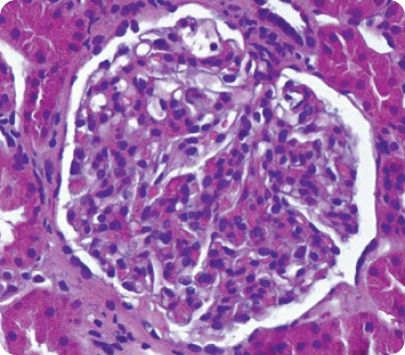

Световая микроскопия6

• Световая микроскопия чаще всего не имеет высокой специфичности и не дает возможность сформировать однозначное заключение о природе почечного заболевания.

• Определяются мембранопролиферативные изменения, мезангиальная и эндокапиллярная пролиферация, а также наличие полулуний7.